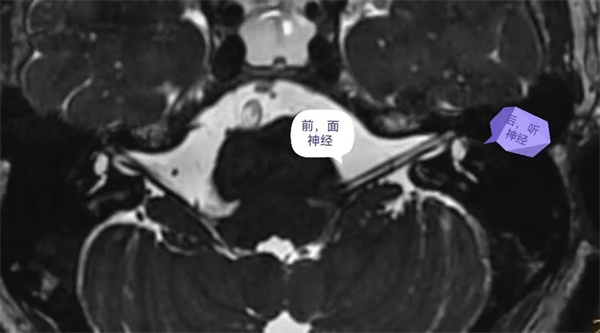

圖3:軸位圖像能清晰顯示、分辨顱內(nèi)腦池段、內(nèi)耳道段面神經(jīng)(前)和聽神經(jīng)(后)。

圖4:神經(jīng)軸位顯示面聽神經(jīng)走形及分支,面神經(jīng)(前上)、耳蝸神經(jīng)(前下)、前庭上神經(jīng)(后上)、前庭下神經(jīng)(后下)。